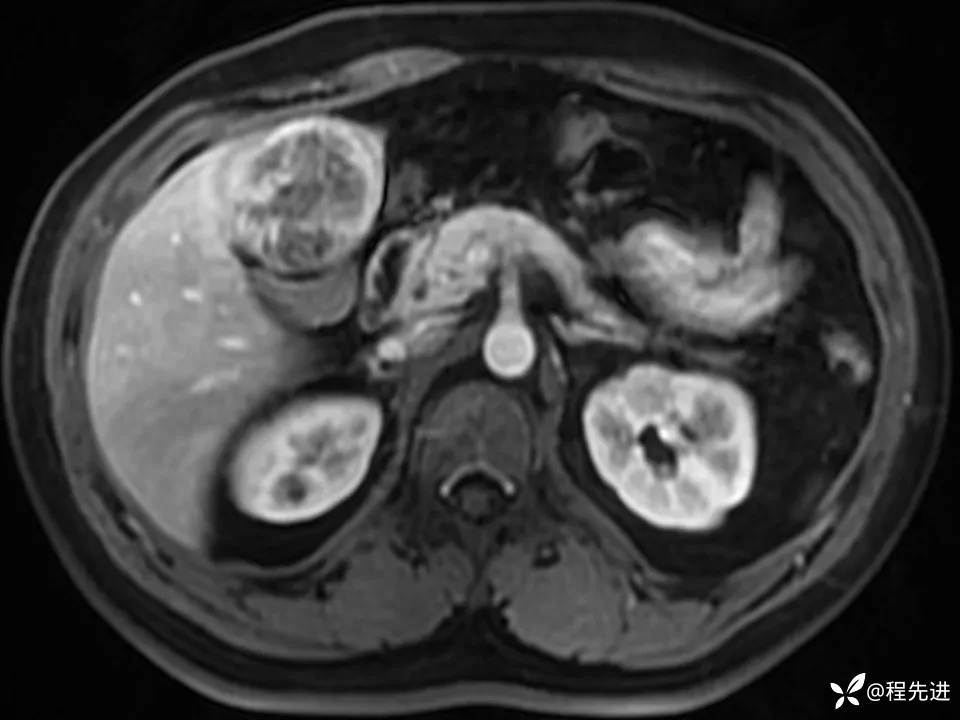

患者性别:男

患者年龄:27岁

简要病史:体检发现肝脏占位2周

既往史:平素体健,无特殊

实验室检查:(-)